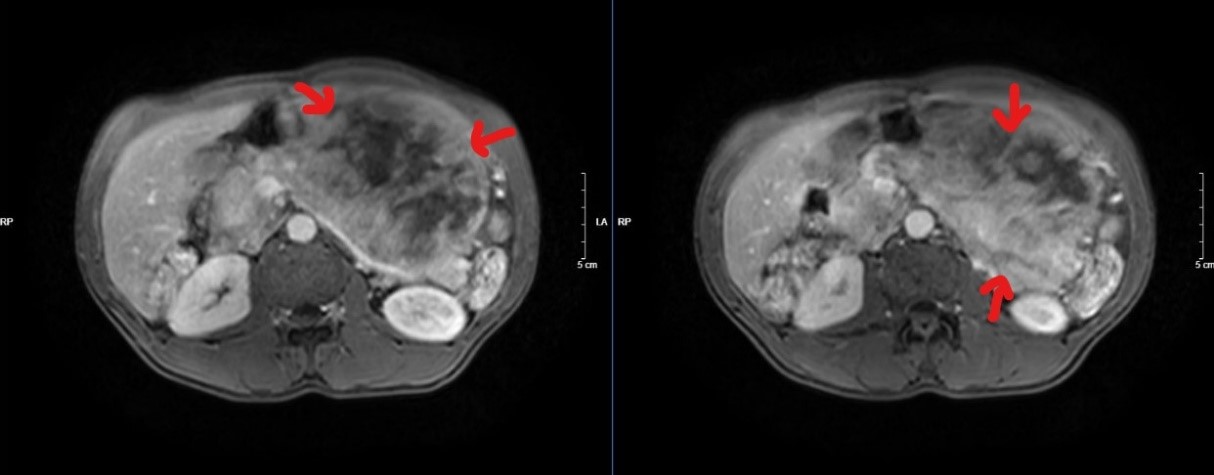

Hình 1: Phim cộng hưởng từ – Hình ảnh khối lớn nửa bụng trái xâm lấn tụy

Trường hợp thứ nhất: Bệnh nhân N, nam 47 tuổi. Tiền sử viêm dạ dày nhiều năm, điều trị không thường xuyên. Khoảng 6 tháng gần đây, bệnh nhân thấy đau tức vùng thượng vị, hay đầy bụng, ăn uống kém hơn. Bệnh nhân tự mua thuốc điều trị viêm dạ dày nhưng không đỡ, đến khi tự sờ thấy khối ở vùng thượng vị mới quyết định đi khám tại Khoa Phẫu thuật Tiêu hóa – Gan mật tụy, Bệnh viện Bạch Mai và được chẩn đoán: GIST dạ dày, tuy nhiên khối u lớn, ở giai đoạn muộn nên đã xâm lấn vào thân đuôi tụy.

Bệnh nhân đã phải trải qua một cuộc phẫu thuật lớn: mổ mở cắt cả khối gồm toàn bộ dạ dày, thân đuôi tụy và lách, ca mổ phức tạp, tuy diễn ra thành công ngoài mong đợi nhưng chặng đường tiếp theo với anh N sẽ nhiều khó khăn, nguy cơ bệnh dễ tái phát hoặc di căn…